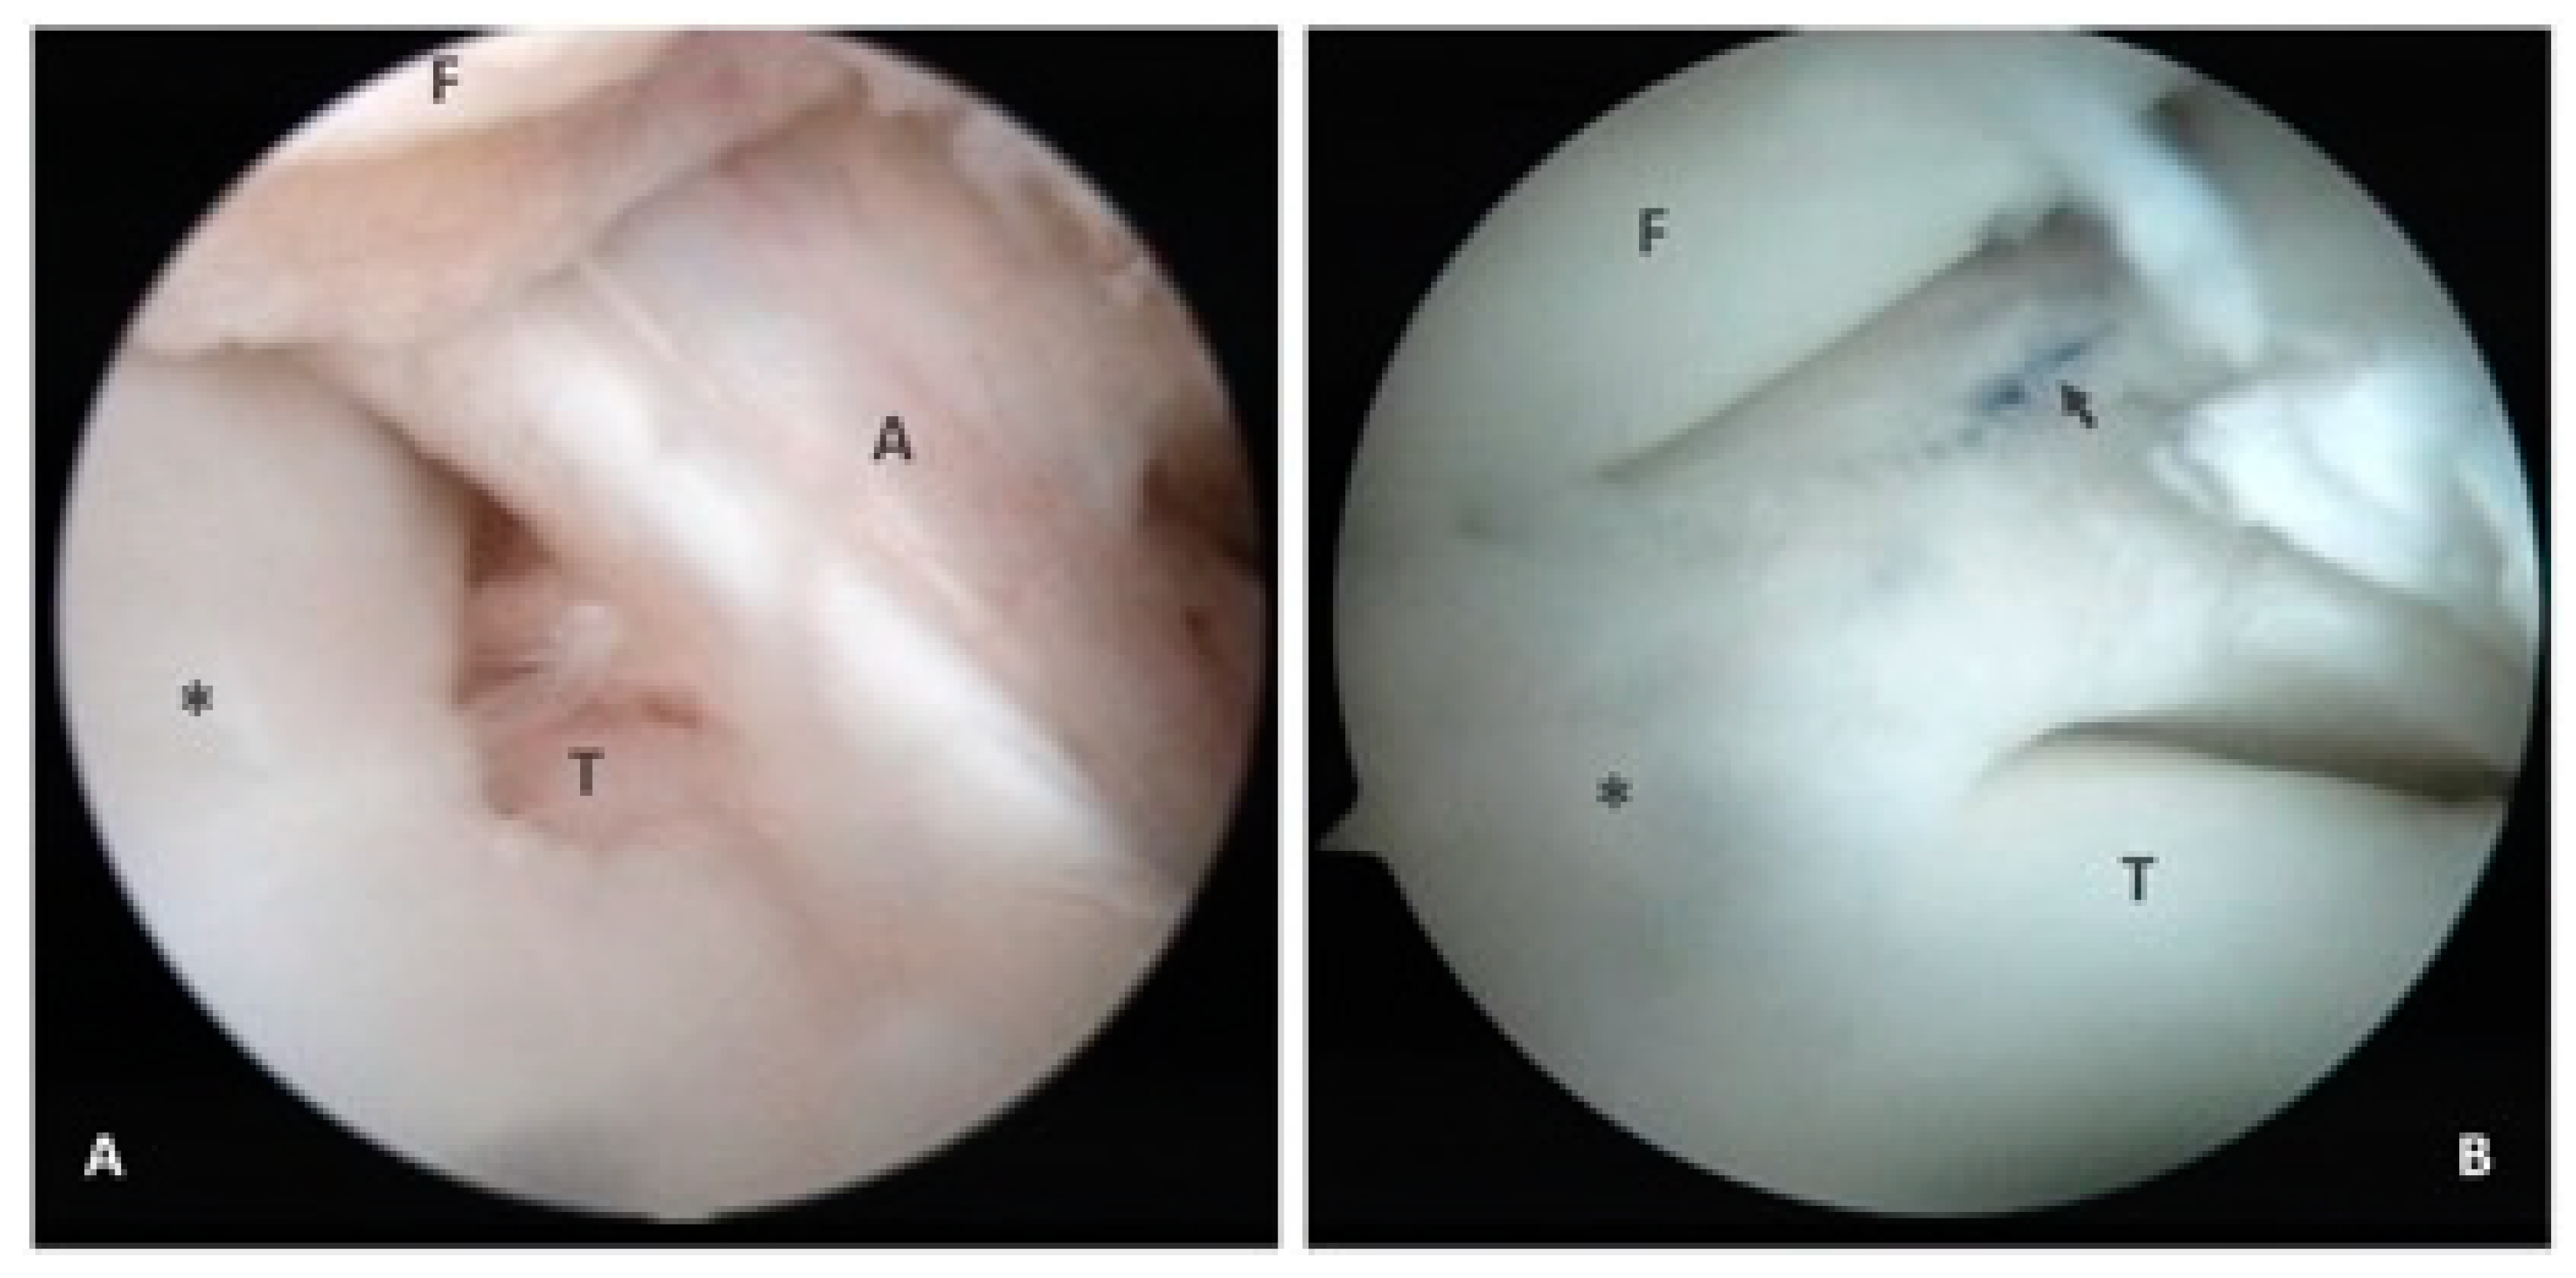

2.1. Case 1

2.2. Case 2